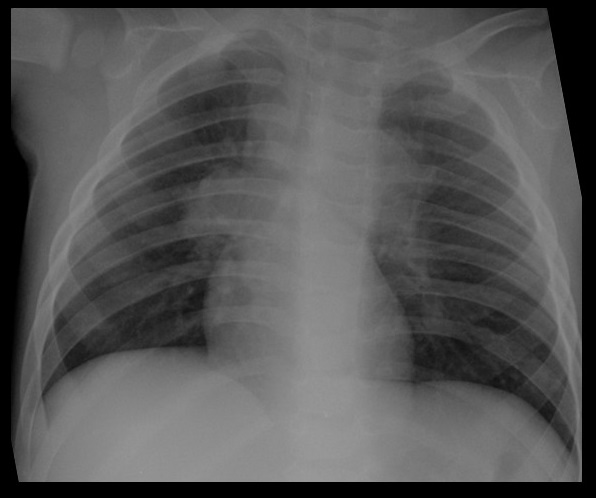

Primoinfección tuberculosa en niño de un año

Lo más frecuente en niños es la primoinfección, adquirida por inhalación de Mycobacterium tuberculosis.

La afectación del parénquima pulmonar no es habitual, pero se puede manifestar como un infiltrado alveolar, asociado o no a derrame.

Las adenopatías hiliares y/o mediastínicas son con frecuencia la única manifestación radiológica en niños. Observaremos un aumento del tamaño de los hilios, con ocupación de la región paratraqueal o subcarinal, con horizontalización de los bronquios principales.